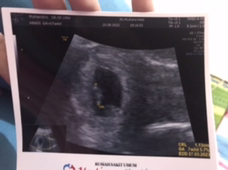

USG kehamilan

Saya dudah USG bun kemarin diusia 8minggu.